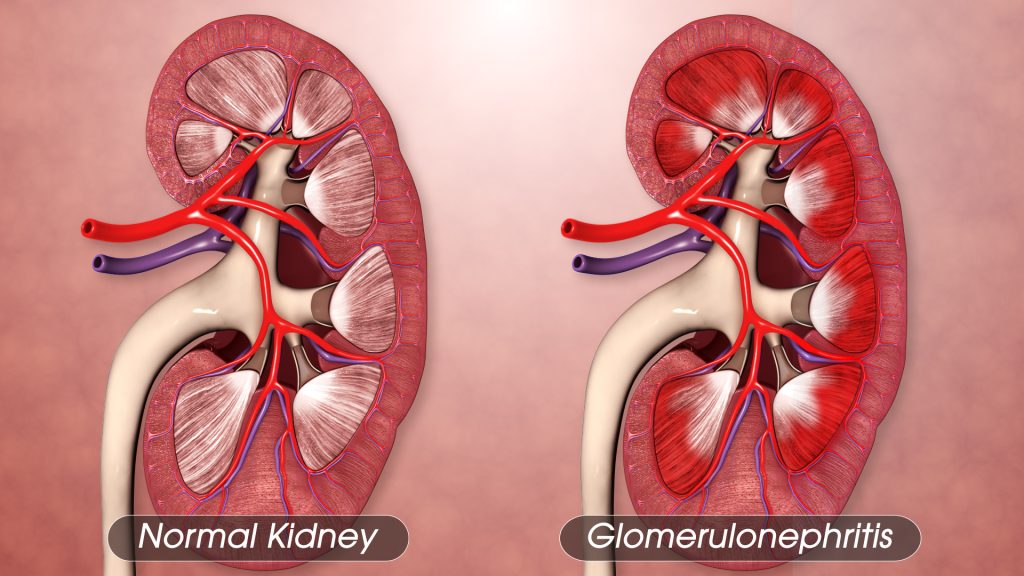

Glomerulonephritis Treatment

Glomerulonephritis treatment depends on the specific type and cause of the condition. In many cases, managing underlying infections or immune system disorders is essential. Medications such as corticosteroids or immunosuppressants may be prescribed to reduce inflammation and immune system activity. Blood pressure control is crucial to protect the kidneys, often achieved through medications like ACE inhibitors or angiotensin II receptor blockers.